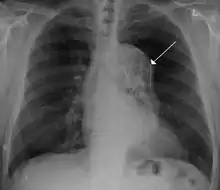

Advances in vascular surgery, specifically endovascular technologies, have led to a dramatic change in the operative approach to blunt thoracic aortic injury (BTAI). BTAI results from a high speed insult to the thorax such as a motor vehicle collision or a fall from a height. One widely-used classification scheme is based on the extent of injury to the anatomic layers of the aorta as seen with computed tomography angiography or intravascular ultrasound. Grade 1 BTAI are those which tear the aortic intima; grade 2 injuries refer to intramural hematoma; grade 3 injuries are pseudoaneurysm and are only contained by adventitial tissue; and grade 4 refer to free rupture of blood into the chest and surrounding tissue.[36] When indicated, first line intervention involves TEVAR.